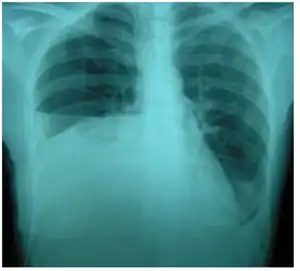

| Right sided pleural effusion caused by urinothorax | |